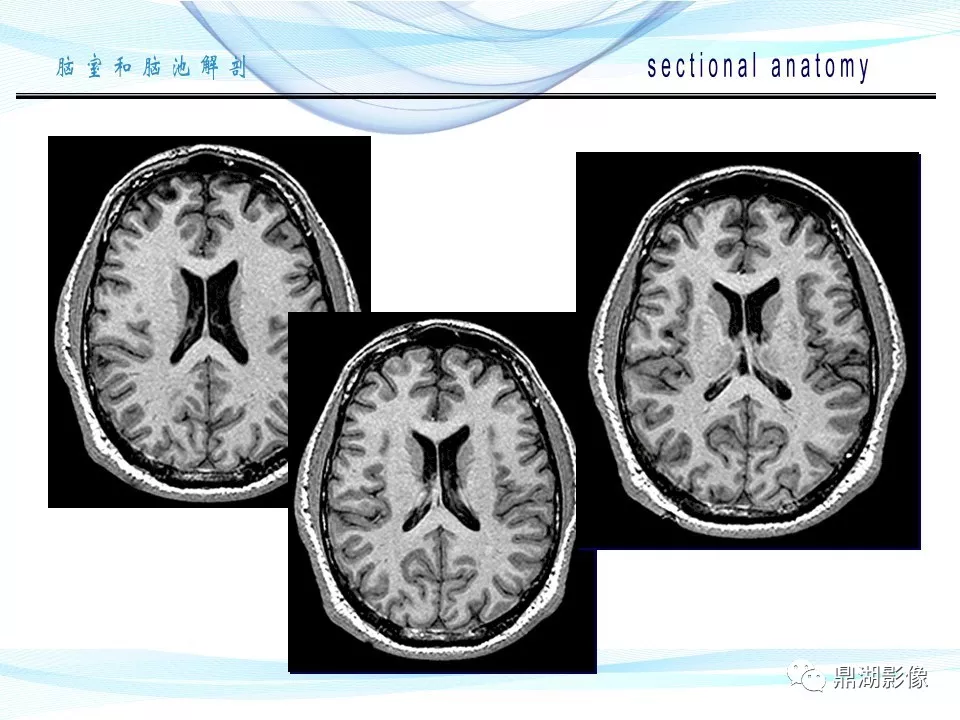

必点收藏 | 脑池和脑室断层解剖

超全详解:脑池和脑室断层解剖